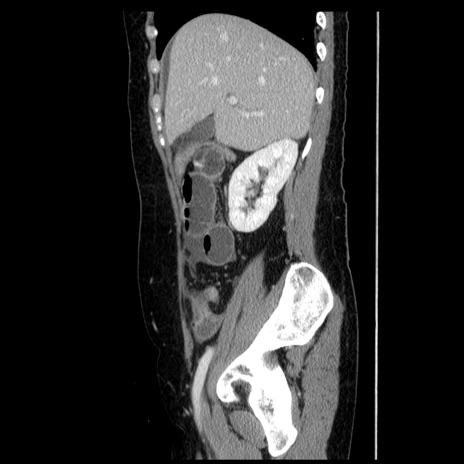

症例

【症例】50歳代女性

【主訴】下腹部痛

【現病歴】本日朝より下痢2回あり。 昼食を食べた後、嘔吐3回、下腹部痛認め、症状軽快せず、当院救急搬送。

最終食事:本日昼(生ものなし)。 昨日の夜、刺身を食ぺたとのこと。周囲に同様の症状の者なし。普段、排便は毎日あるとのこと。

【既往歴】卵巣癌術後(8年前に当院で卵巣摘出)

【身体所見】 意識清明、腹部:平坦、腸蠕動音→、やや硬、下腹部自発痛・圧痛あり、反跳痛あり、筋性防御なし。

【データ】WBC 16000、CRP 0.01

冠状断像